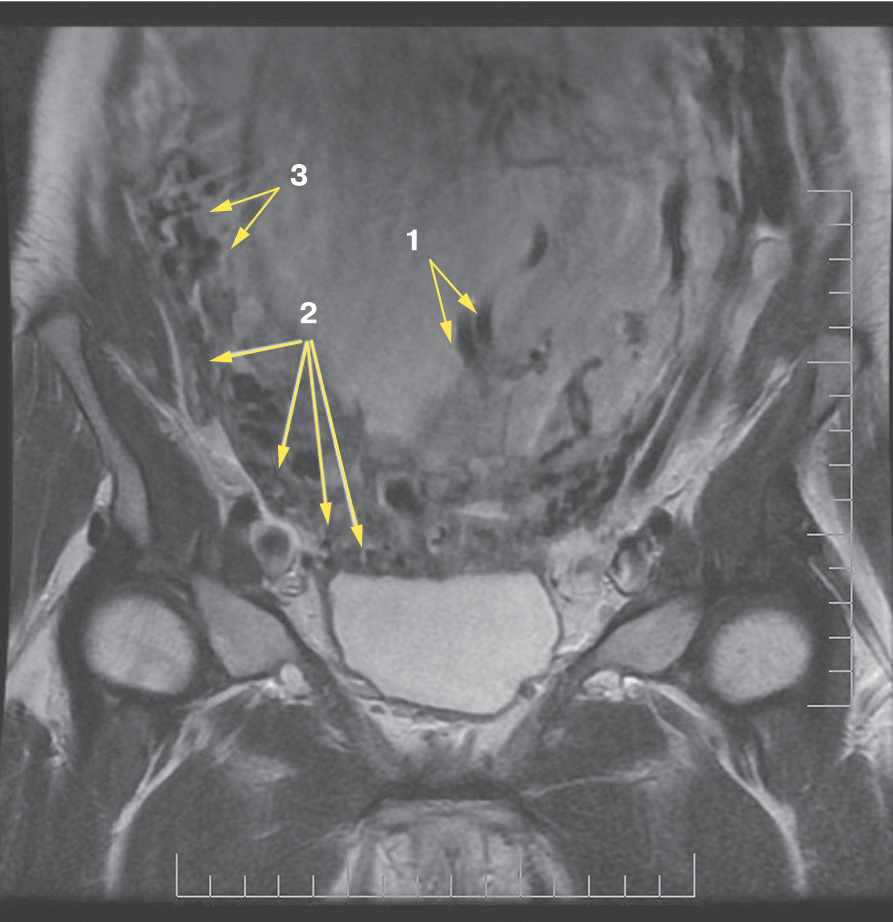

Также стоит выделить особый тип плацентарной гиперваскуляризации, а именно включение в плацентарной ткани изменений по типу «обнаженного сосуда» (рис. 1, 2). Мы провели анализ встречаемости данного признака среди наших пациентов. Любопытным наблюдением явилось то, что данный симптом в нашей выборке встречался только при наличии placenta percreta – 6 случаев, а именно при поражении параметриев, и не встречался при плацентарной инвазии, ограниченной миометрием. «Мостовидные сосуды» были менее специфичны, тем не менее, их наличие также сопровождало тяжелые формы врастания, обусловленные более глубокой инвазией ворсин хориона, – 8 случаев.

Рис. 1. МРТ placenta percreta, симптом «обнаженного сосуда»

Рис. 2. МРТ placenta percreta, симптом «обнаженного сосуда»

Является ли симптом «обнаженного сосуда» патогномоничным для параметральной инвазии или нет, еще предстоит выяснить; однако в ходе исследования установлена его связь с частотой гистерэктомий в группах с наличием симптома «обнаженного сосуда», что, вероятно, обусловлено мощной сосудистой сетью коллатералей и неоангиогенезом. Во всех случаях обнаружения данного признака впоследствии была выполнена вынужденная гистерэктомия (рис. 3–6, пациентка Н., 37 лет).

Рис. 5. Корональная проекция МРТ. 1 – интрамуральная гиперваскуляризация; 2- измененный контур мочевого пузыря

Рис. 6. Корональная проекция МРТ. 1 – обнаженный сосуд; 2 – интрамуральная гиперваскуляризация; 3 – гиперваскуляризация плаценты